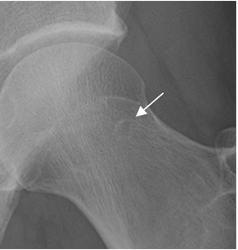

Fig 104. Pinzamiento tipo cam. Angulo alfa normal.

RM axial oblicua de cadera. Trazado entre el eje del cuello femoral y el sitio donde se corta la circunferencia de la cabeza femoral, con el borde lateral.